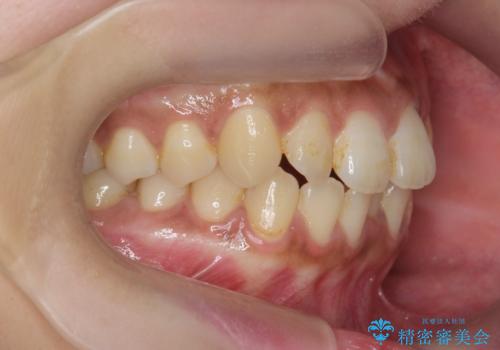

前歯のがたつきをすっきり マウスピース矯正

- 長年気になっていた前歯のがたつきをマウスピース矯正で治したい!と希望され来院されました。

奥歯の噛み合わせには問題がなく、前歯のがたつきの改善のみで十分に審美的な結果が得られるため、ワイヤーではなくマウスピース矯正での治療を計画します。

しっかりと前歯のがたつきは改善し見た目が大きく良くすることができました。